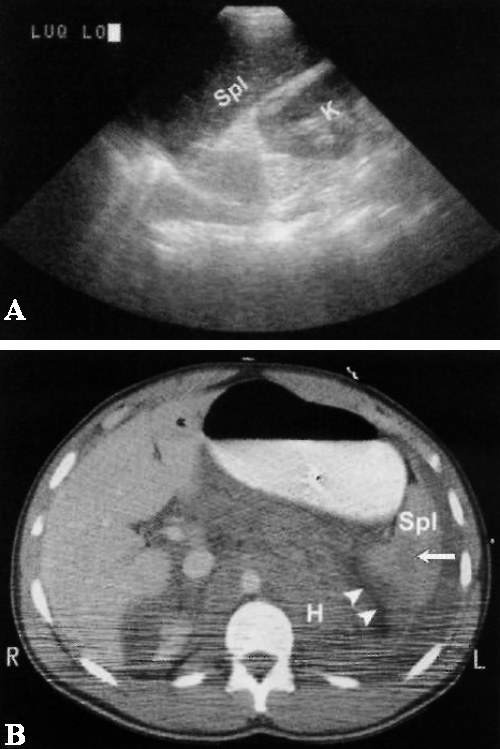

Фото 6. Ложноотрицательное УЗИ. А – продольное ультразвуковое изображение демонстрирует нормальную почку (К) и селезенку (Spl) без признаков наличия свободной жидкости. В – КТ того же пациента, выполненное через 30 минут после УЗИ: стрелкой обозначен разрыв селезенки; указателями отмечена жидкость, скопившаяся вокруг селезенки, и массивная ретроперитонеальная гематома (Н). Также отмечается частичная некротизация правой почки